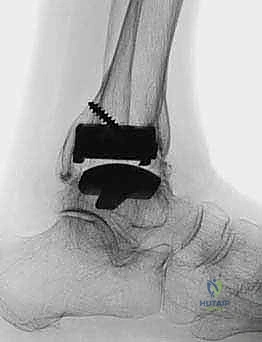

FIG 6 • The TNK ankle replacement for rheumatoid arthritis of the ankle (cemented replacement). A. Preoperative AP view. B. Preoperative lateral view. C. Postoperative AP view 2 years 6 months after the surgery. D. Postoperative lateral view.